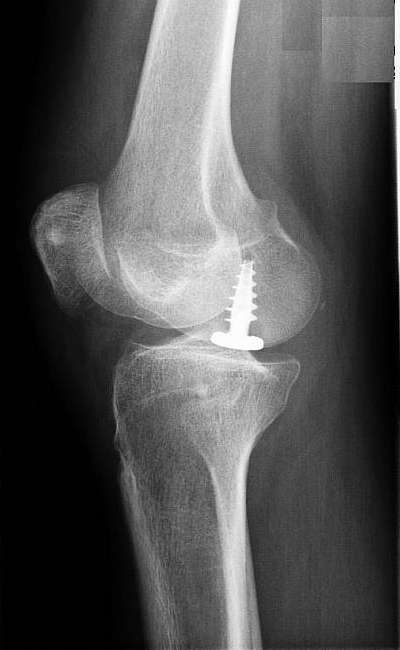

Wenn die retropatellare Arthrose beide Gelenkflächen – Patella und Oberschenkel – betrifft, kommt eine retropatellare Prothese mit patellaseitiger PET-Gleitschicht zum Einsatz. Dieses Röntgenbild zeigt nur die Metallkomponente. Der Kunststoff wird im Röntgen nicht dargestellt. © Prof. Dr. med. Ostermeier

Wenn die patellaseitige Knorpelschicht ebenfalls schon abgenutzt ist, muss die Prothese mit einem Kunststoff-Gleitpartner implantiert werden. Bei der patellofemoralen Prothese verbindet sich das Implantat im Femur (Oberschenkelknochen) mit einer Polyethylen-Gleitschicht, die an der Patella (Kniescheibe) implantiert ist.